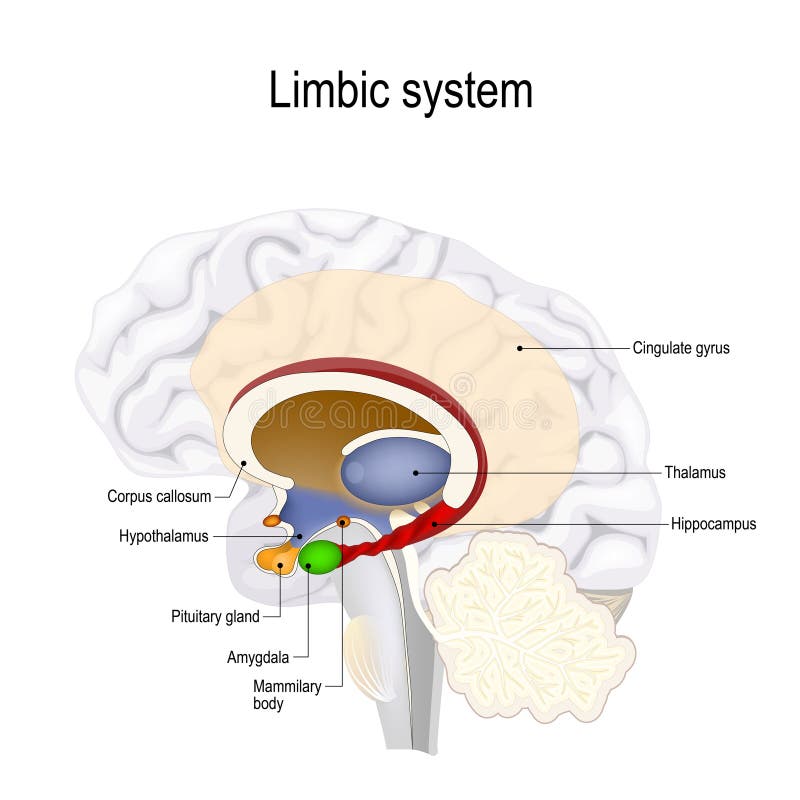

έννοια της τεχνητής νοημοσύνης. άνθρωπος-εγκέφαλος με σύμβολο τεχνητής νοημοσύνης.